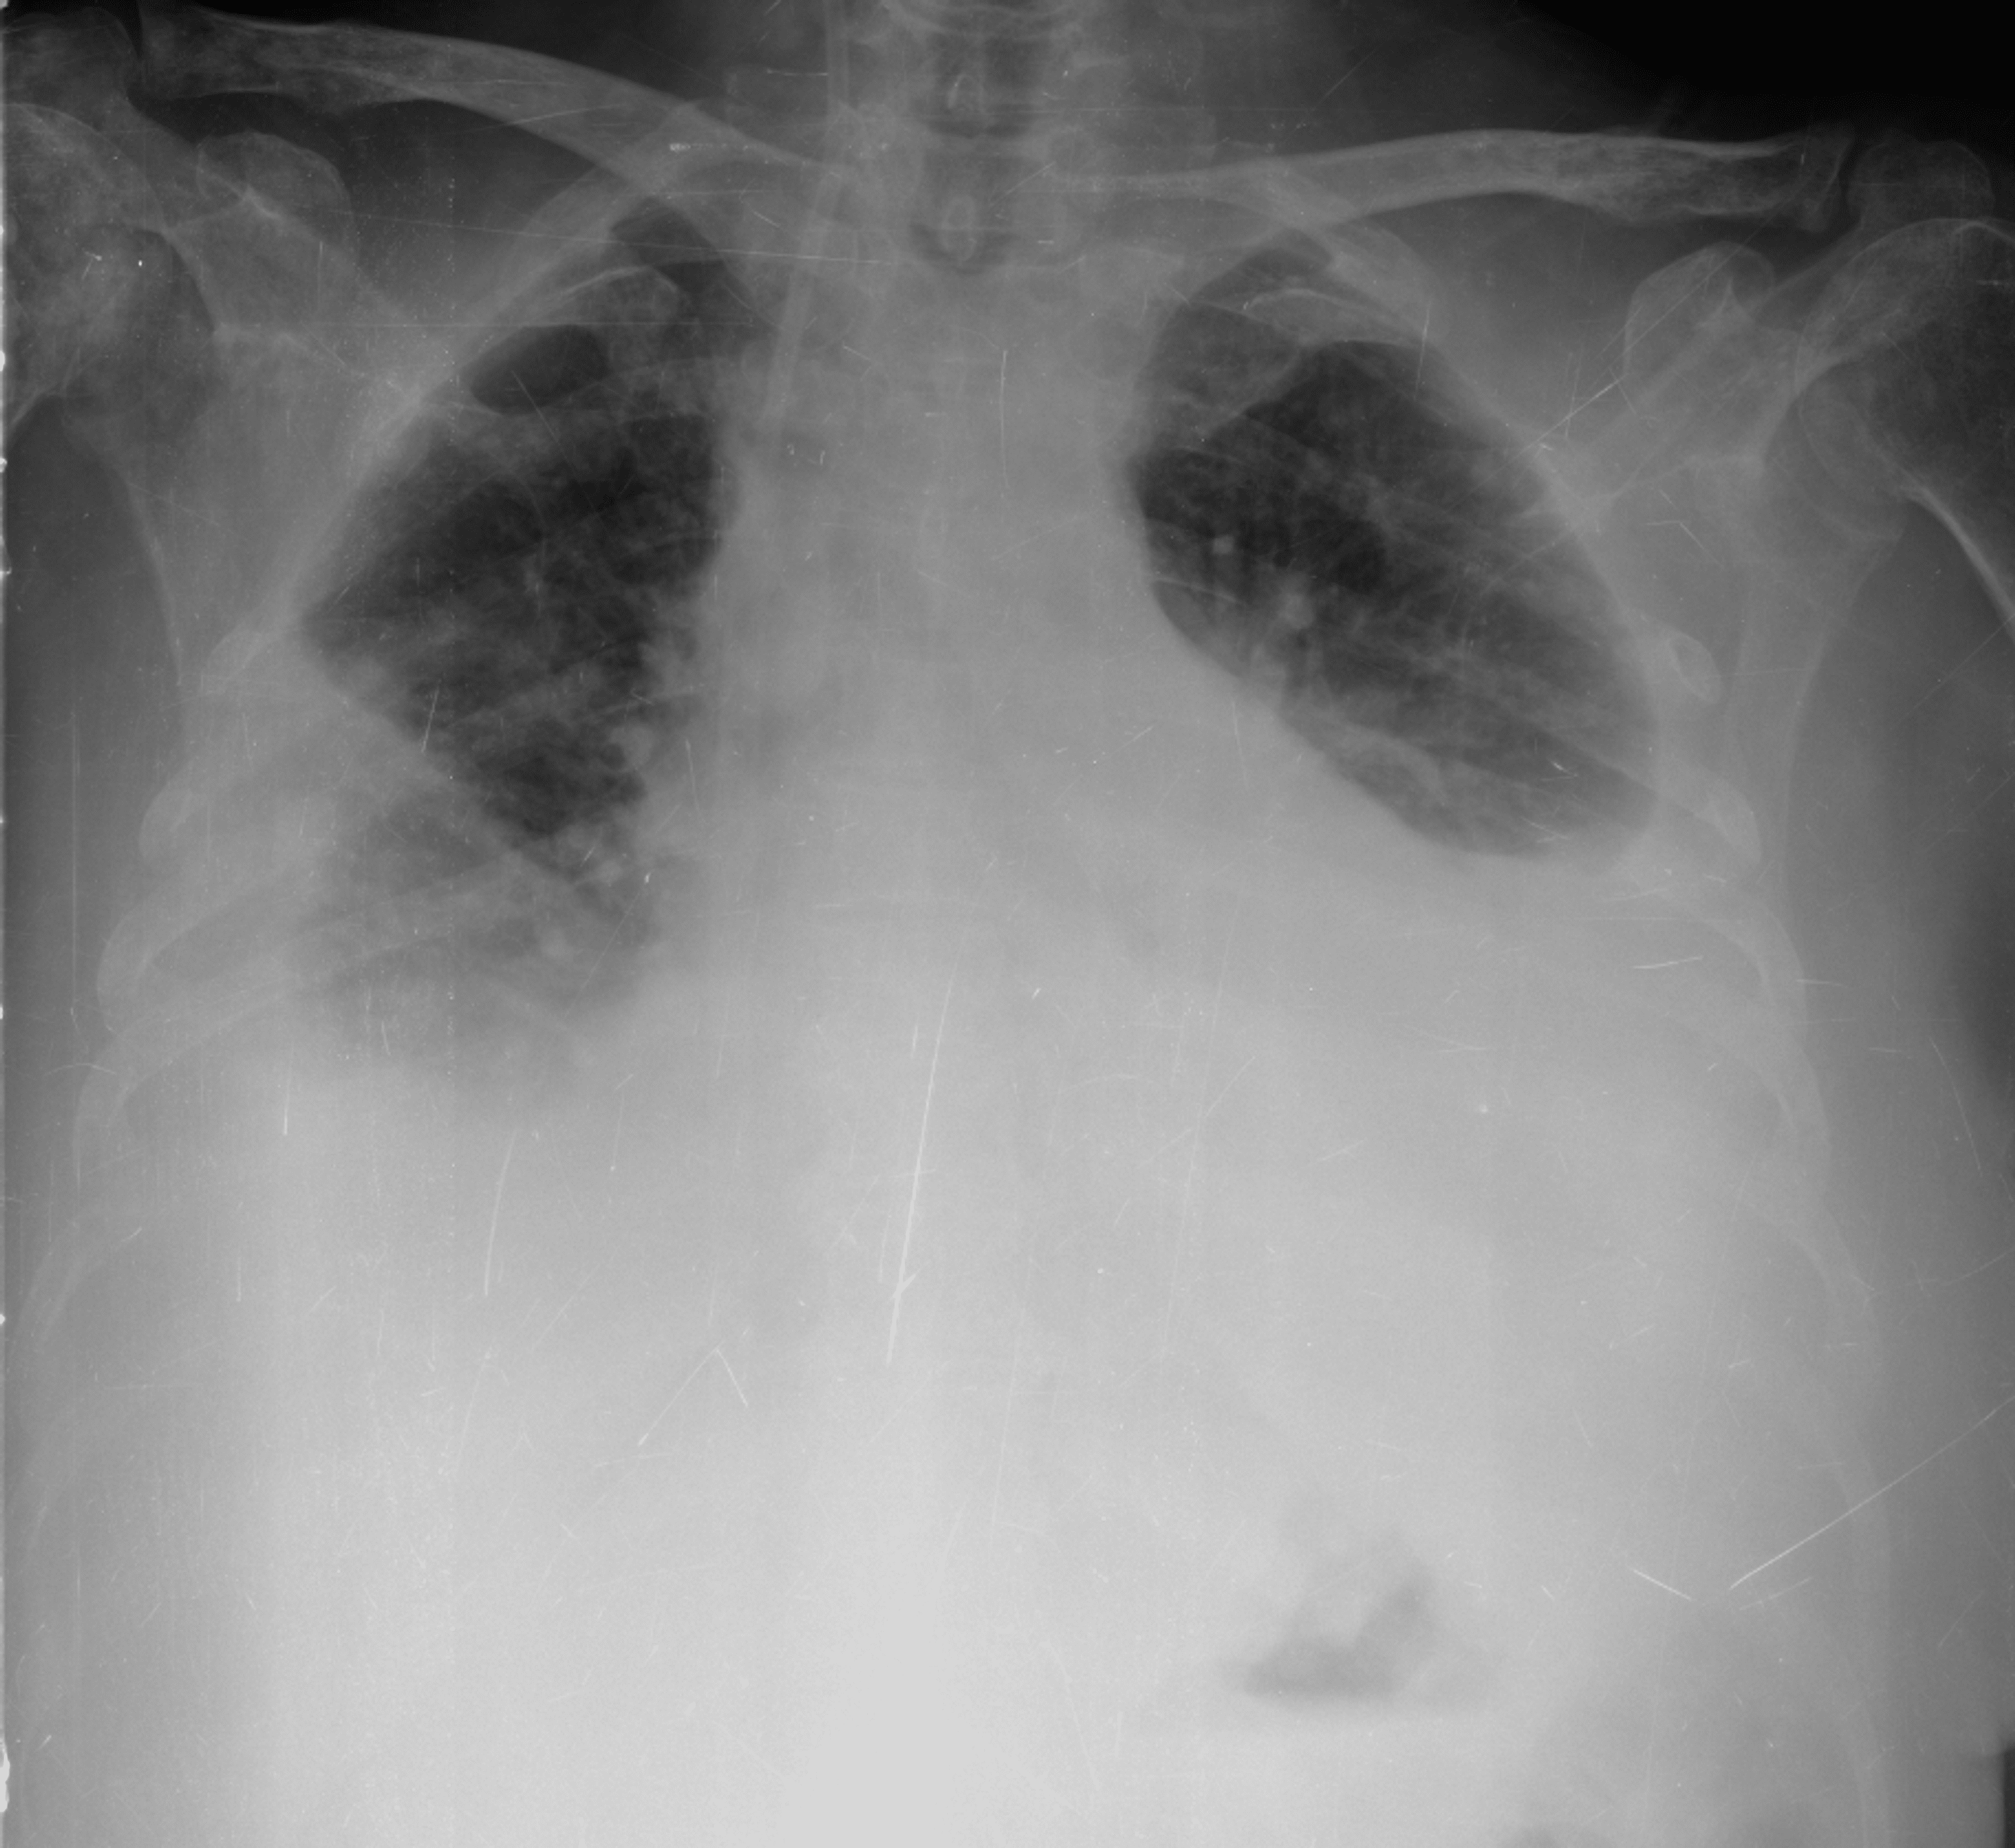

Study Medical Photos Pleural effusion On Chest X ray

Pleural effusions are collections of fluid within the pleural. pleural effusion volume (ml) = distance (cm) x 90 the second goecke formula measures the distance between. pleural effusion occurs when fluid collects between the parietal and visceral pleura. in 32 consecutive patients with a clinical and radiologic diagnosis of. Once the accumulated fluid is more. chest radiographs are the most commonly used examination to assess for the presence of pleural effusion; As much as 500 ml of pleural. pleural effusion associated with congestive heart failure. Healthcare providers use these tests to diagnose and. findings on chest radiographs frequently confirm the presence of pleural effusion.